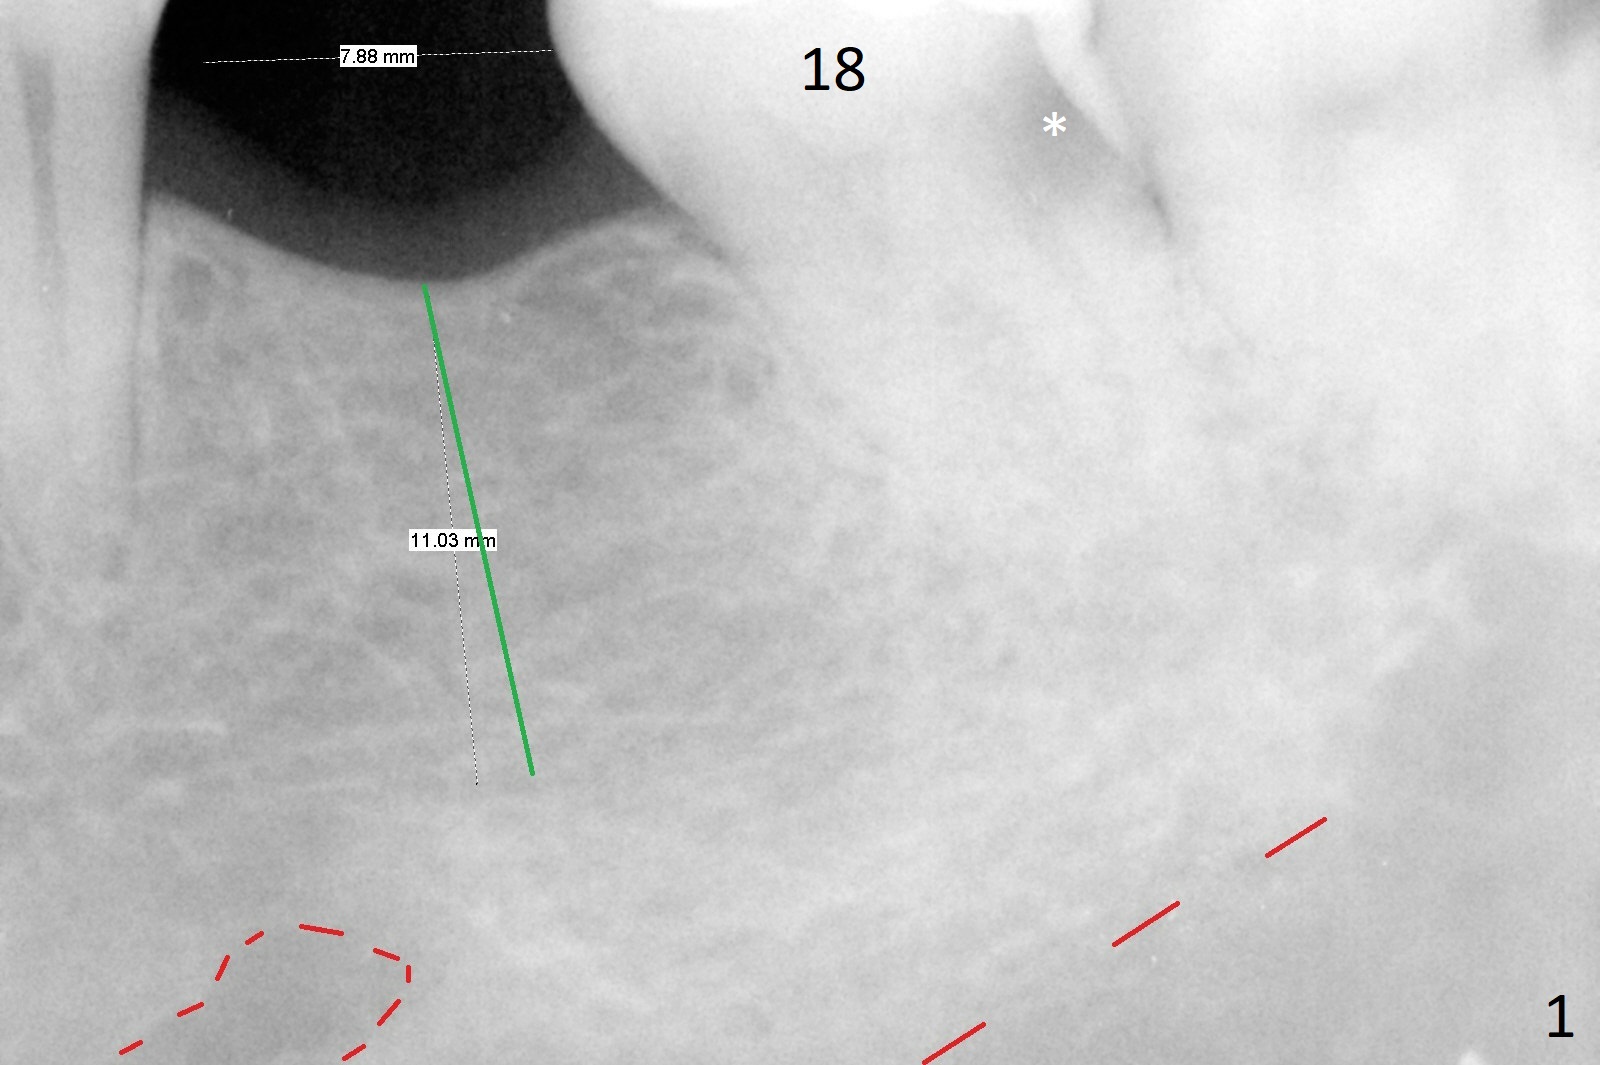

Narrow Implant for Molar

A 53-year-old woman needs an implant at #19, since the implant abutment/crown at #3 becomes loose while a crown is being made for the tooth #18 after RCT (Fig.1). As the mesiodistal space is ~ 8 mm (Fig.1) and the buccolingual width of the ridge is not wide, a narrow implant (e.g., 4x11 mm) is indicated to avoid implant thread exposure. If the osteotomy deviates slightly distal apically (Fig.1 green line vs. dashed line), there is less likelihood of damage to the Mental Loop (red dashed line).